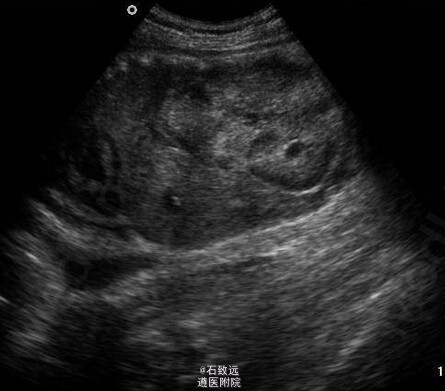

查体:颜面浮肿,双下肢水肿,余无异常。 尿常规示:尿蛋白+++,红细胞0~7HP;24h尿蛋白定量77mg/(kg.d);血总蛋白48.4gL,白蛋白23.4g,L,胆固醇l0.79mmolL,肌酐53.04txmolL,尿素氮7.14mmol/L。B超如图。双肾各探及多个大小不等的囊性无回声区。

诊断:1、多囊肾 2、肾病综合征 处理:入院后予曲安西龙16mg,3次/d,监测血压波动在96~132到60~86mmHg,加服卡托普利25mg,1次12h,血压平稳,住院11d自动出院,出院时尿蛋白+++。 考虑该病家族性聚集,嘱其母至当地医院行腹部B超。